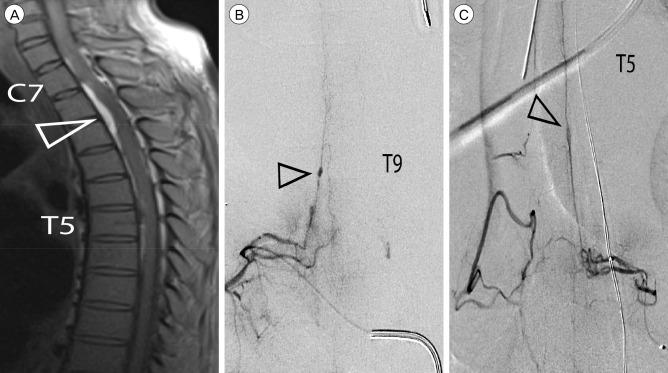

Rupture of isolated posterior spinal artery (PSA) aneurysms is a rare cause of subarachnoid hemorrhage (SAH) that presents unique diagnostic challenges owing to a nuanced clinical presentation. Here, we report on the diagnosis and management of the first known case of an isolated PSA aneurysm in the context of leukocytoclastic vasculitis. A 53-year-old male presented to an outside institution with acute bilateral lower extremity paralysis 9 days after admission for recurrent cellulitis. Early magnetic resonance imaging was read as negative and repeat imaging 15 days after presentation revealed SAH and a compressive spinal subdural hematoma. Angiography identified a PSA aneurysm at T9, as well as other areas suspicious for inflammatory or post-hemorrhagic reactive changes. The patient underwent a multilevel laminectomy for clot evacuation and aneurysm resection to prevent future hemorrhage and to establish a diagnosis. The postoperative course was complicated by medical issues and led to the diagnosis of leukocytoclastic vasculitis that may have predisposed the patient to aneurysm development. Literature review reveals greater mortality for cervical lesions than thoracolumbar lesions and that the presence of meningitic symptoms portents better functional outcome than symptoms of cord compression. The outcome obtained in this case is consistent with outcomes reported in the literature.

孤立性脊髓后动脉(PSA)动脉瘤破裂是蛛网膜下腔出血(SAH)的罕见原因,因其临床表现细微而带来独特的诊断挑战。在此,我们报告了在白细胞破碎性血管炎背景下首例已知的孤立性PSA动脉瘤的诊断与治疗情况。一名53岁男性因复发性蜂窝织炎入院9天后,在外院出现急性双侧下肢瘫痪。早期磁共振成像检查结果为阴性,就诊15天后复查成像显示有SAH和压迫性脊髓硬膜下血肿。血管造影显示T9水平有一个PSA动脉瘤,以及其他可疑为炎症或出血后反应性改变的区域。患者接受了多级椎板切除术以清除血块并切除动脉瘤,以防止未来出血并明确诊断。术后病程因医疗问题而复杂化,最终诊断为白细胞破碎性血管炎,这可能是患者发生动脉瘤的诱因。文献综述显示,颈椎病变的死亡率高于胸腰椎病变,且脑膜症状患者的功能预后比脊髓压迫症状患者更好。本病例的治疗结果与文献报道的结果一致。